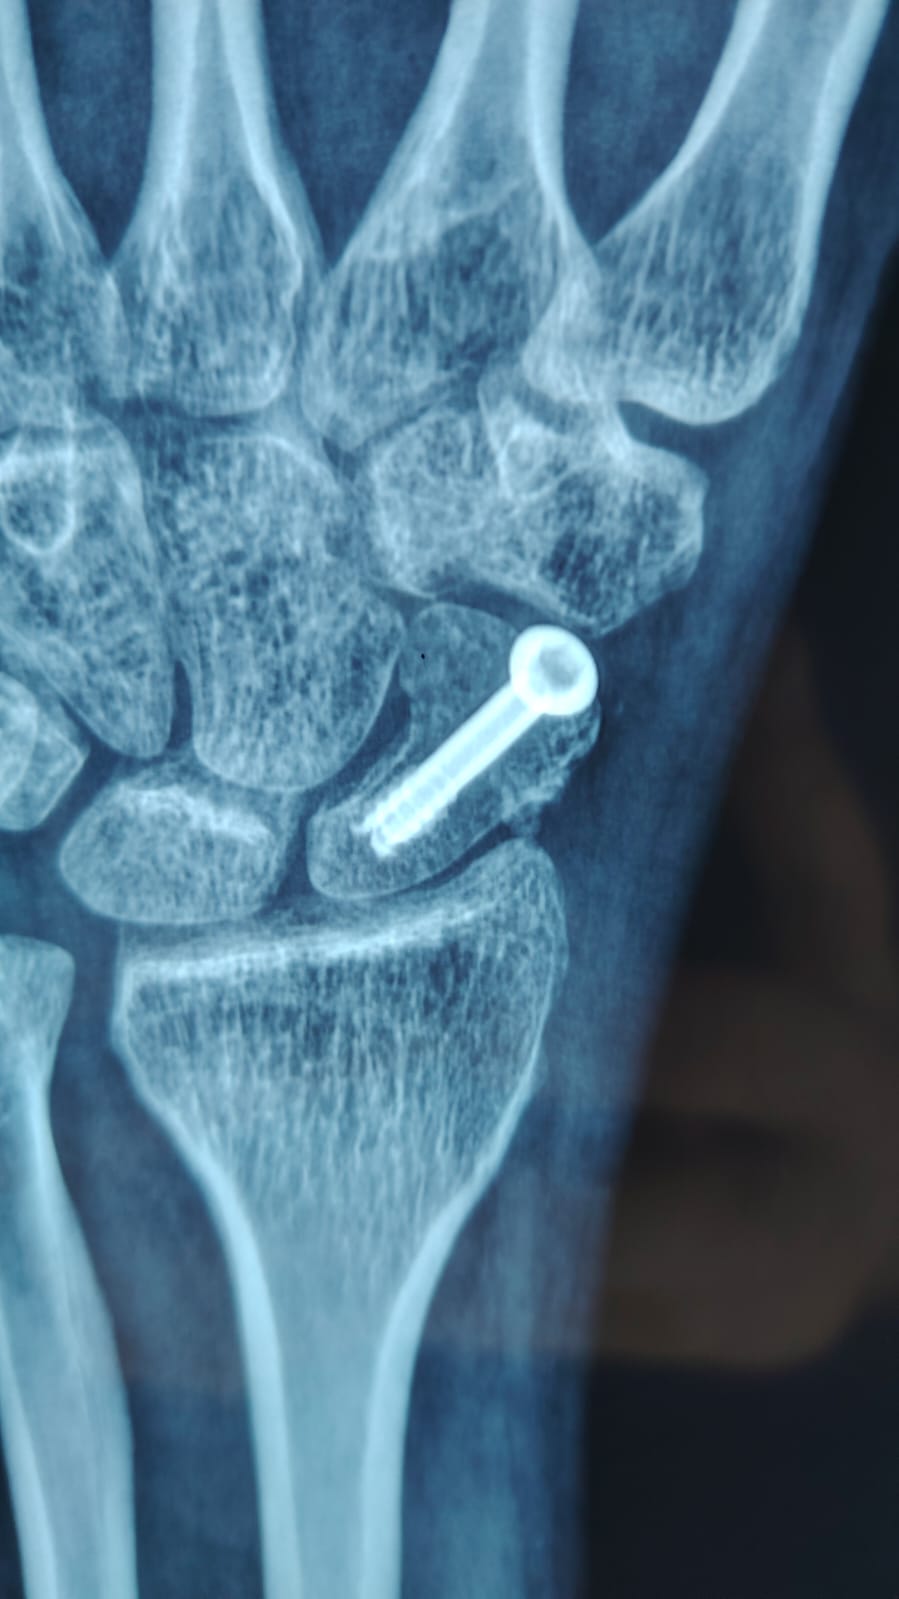

Imagen de fractura de hueso escafoides de la mano manejada con Tornillo Canulado